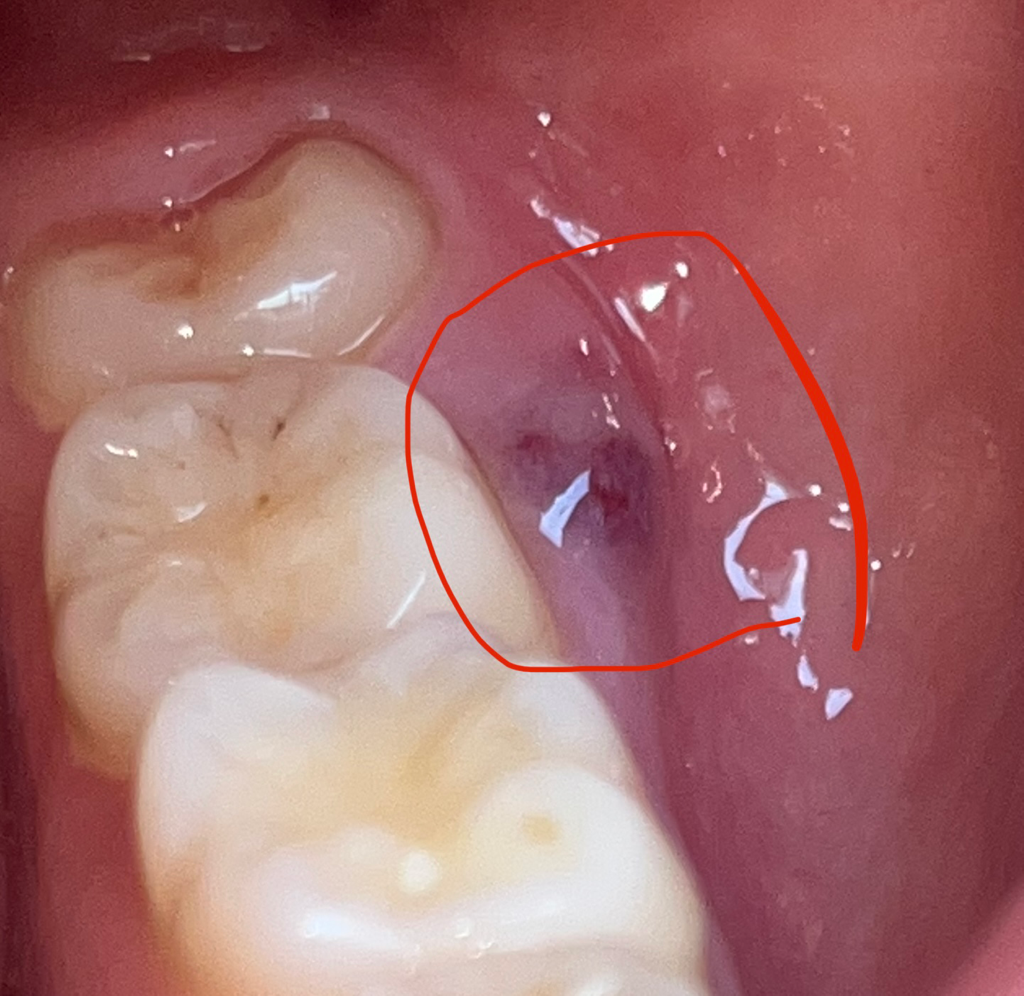

어금니 옆 잇몸에 뭐가 났습니다

어금니 옆에 잇몸이 아파서 봤는데 사진처럼 뭐가 나있습니다. 이게 왜 그러는 건가요???? 병원에 가봐야하나요? 아님 시간지나면 사라지나요?

잇몸에 염증이 생기면서 발생한 것일 수도 있겠습니다.

치과에 가셔서 전문의의 진찰과 검사를 받아보세요.